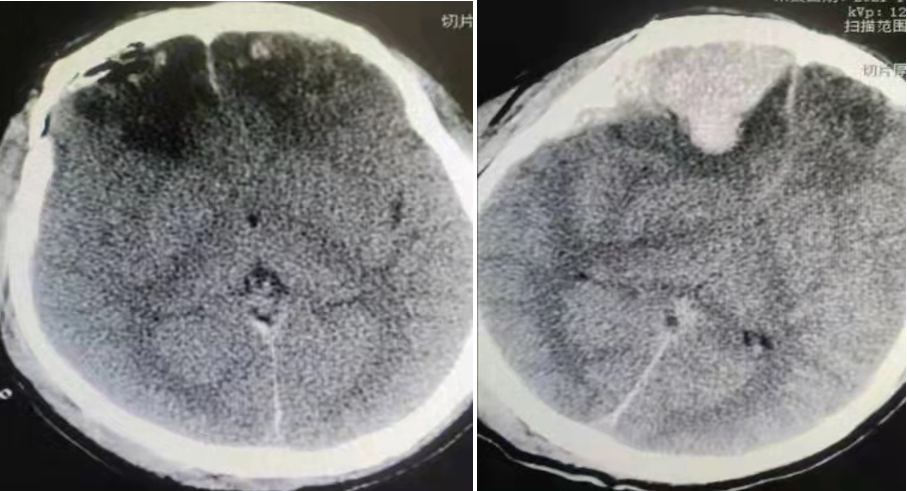

患者男性,43岁,因车祸昏迷脑疝入院,经急诊CT显示颅内硬膜下出血,出血量超过60ml。生死攸关之际,神经外科赵程欣、张永哲、李兵桥三位医生紧急进行术前讨论、分析病情,迅速制定救治方案,在与家属进行了充分沟通后,决定急诊行神经内镜联合显微镜脑内血肿清除术,以最小创伤,争取最大治疗机会。

手术由神经外科主任医师赵程欣与主治医师李兵桥共同完成,术中二人默契配合、紧密协作。因脑部血管和神经组织极为丰富,需要在狭窄的手术区域内辨认和避开正常的血管和神经组织,并清除患者脑内血肿,每一步操作都要求精确无误,因此对术者的医疗技术与心理素质都要求极高。历时两个多小时,手术顺利完成,术后一天复查CT,颅内出血完全清除,患者左侧肢体活动自由,恢复良好,目前已痊愈出院。